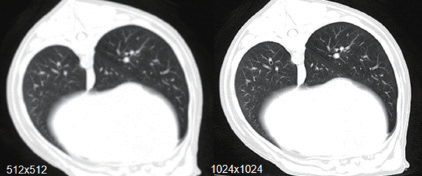

超大视野建像

1024*1024超大视野,独家的 60KV 低剂量扫描技术,普通CT普遍采用80KV低剂量技术

对婴宠物扫描,重要器官保护作用

体检肺部低剂量扫描, 筛查对患者都有巨大保护作用